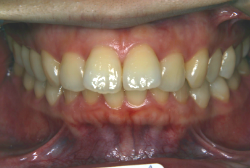

叢生(そうせい)

凸凹な歯並びのことを叢生といいます。矯正歯科に来院する患者様の主訴の中で、最も多いのが「配列の凸凹を真っ直ぐにしたい」というものです。歯の大きさと顎の大きさの調和がとれていないことが原因です。

凸凹を主体としたケースの場合、当院の平均治療期間は18ヶ月ですので、このケースは少し長めに経過しました。理由の一つは凸凹の程度がかなり重症だったと言うことですが、もう一つは、右下第2大臼歯が45度くらい前傾していたため、それを整直化させるために時間を要したと考えています。いずれにしても最終結果は大変よい状態と思います。

治療前は並びが乱れて見た目が悪いというのはもちろん問題ですが、歯科医学的に一番困るのは噛み合わせが悪いという点です。上下の犬歯(3番目の歯)は、上下的に離れた位置にあるため接触することができません。つまり歯としては存在していても、歯としては機能していないということです。